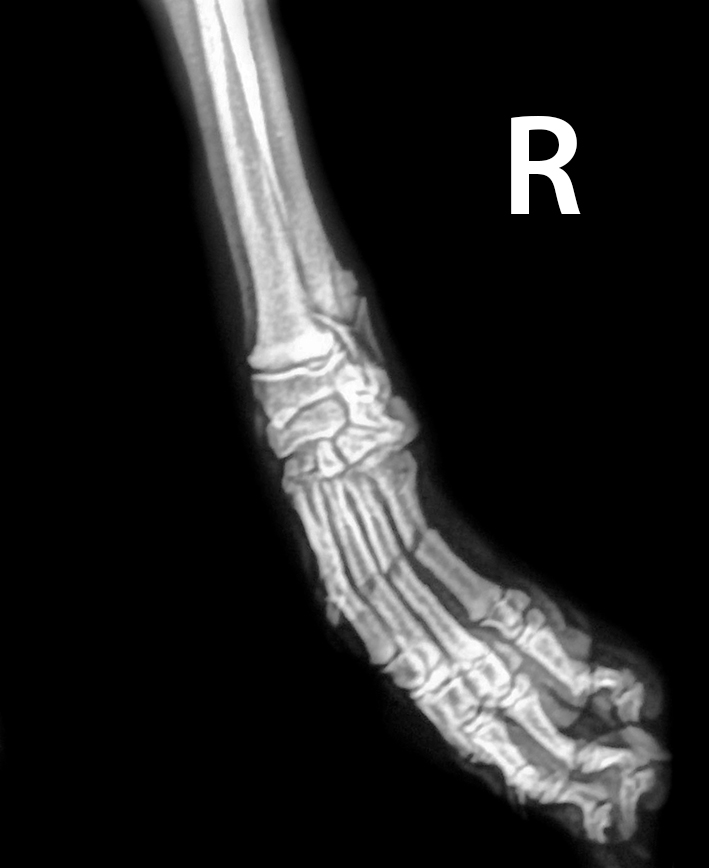

Al acudir a la clínica se le hace una primera radiografía y

nos encontramos con esta fractura:

Se trata de una fractura diafisaria transversa de los

metacarpos II, III, IV y V de su extremidad anterior derecha.